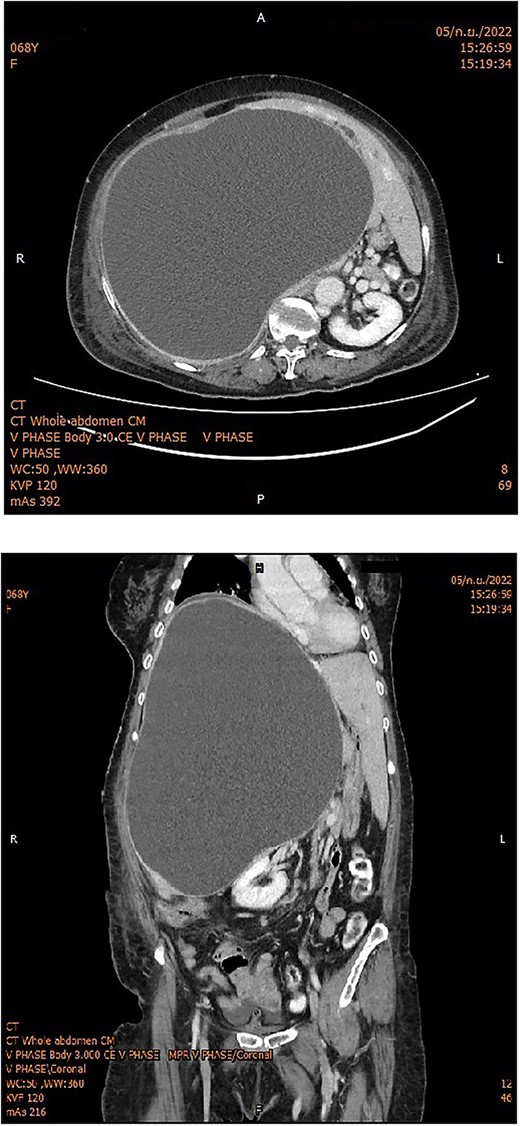

The subsequent endoscopic retrograde cholangiopancreatography showed no filling defect or luminal narrowing (Fig. 2). Pathological examination of the cyst wall revealed a benign cyst lined by cuboidal cells with acute chronic inflammation (Figs 4 and 5).

Cholangiography showed a smooth common bile duct wall without intraluminal filling defects.